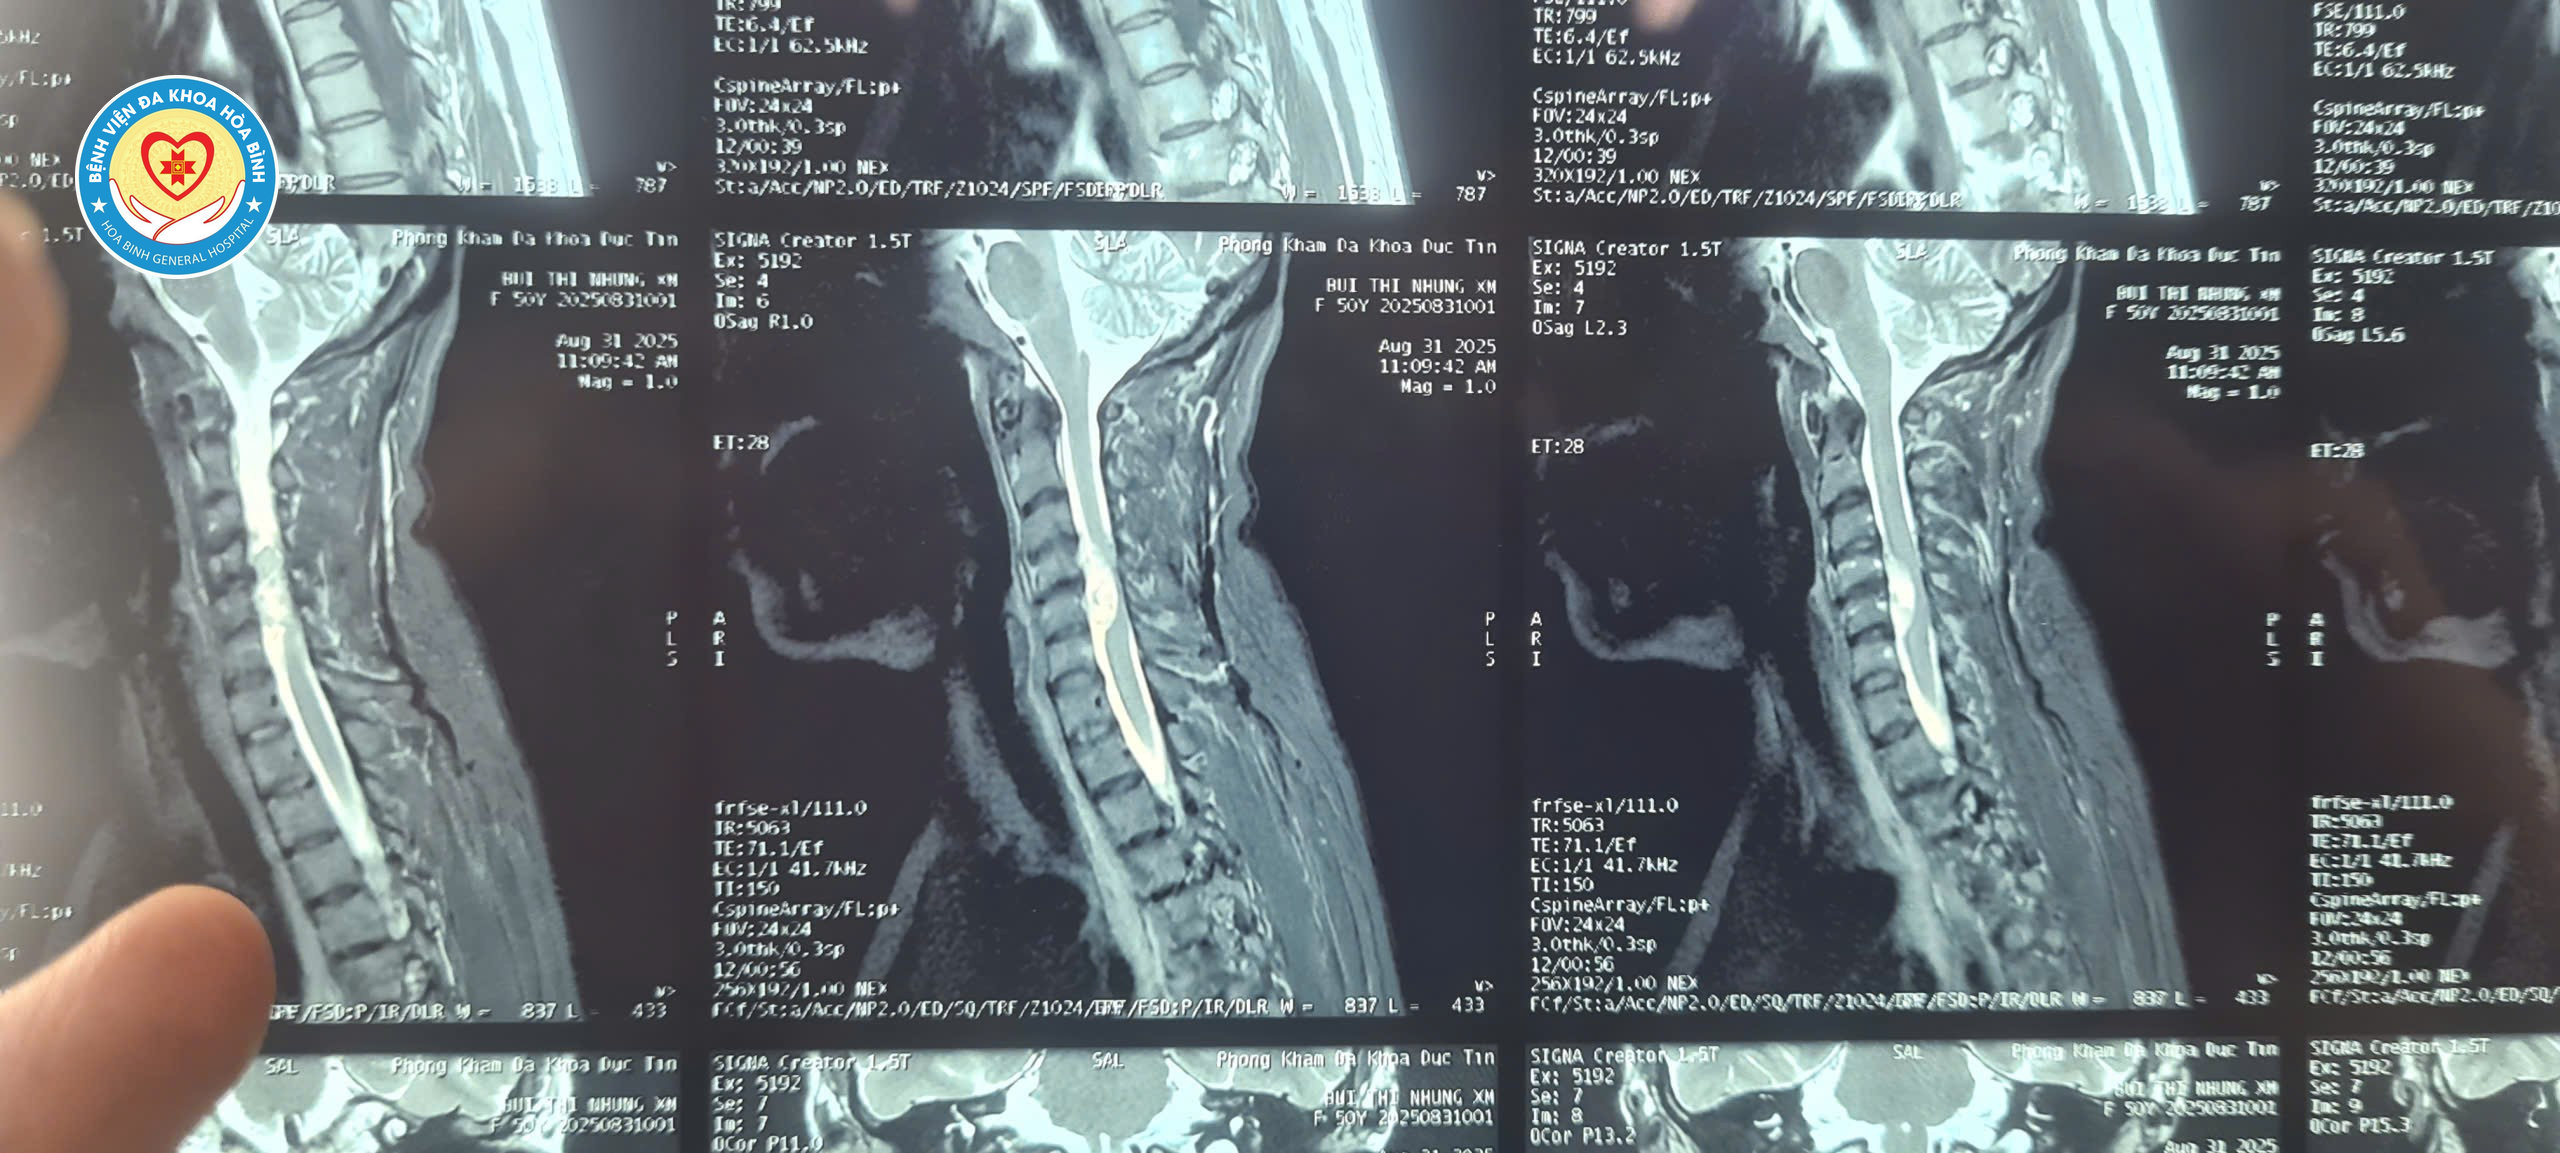

Bệnh nhân nhập viện trong tình trạng tay chân yếu, đi lại khó khăn, tay phải liên tục bị đau và co giật do khối u chèn ép mạnh vào tủy sống. Kết quả chụp Cộng hưởng từ cho thấy khối u nằm ở mặt trước tủy sống cổ C4/5, chiếm tới 2/3 diện tích ống sống, gây chèn ép nặng nề và nguy cơ liệt tứ chi nếu không được can thiệp kịp thời.

Hình ảnh khối u tủy cổ trên phim chụp Cộng hưởng từ